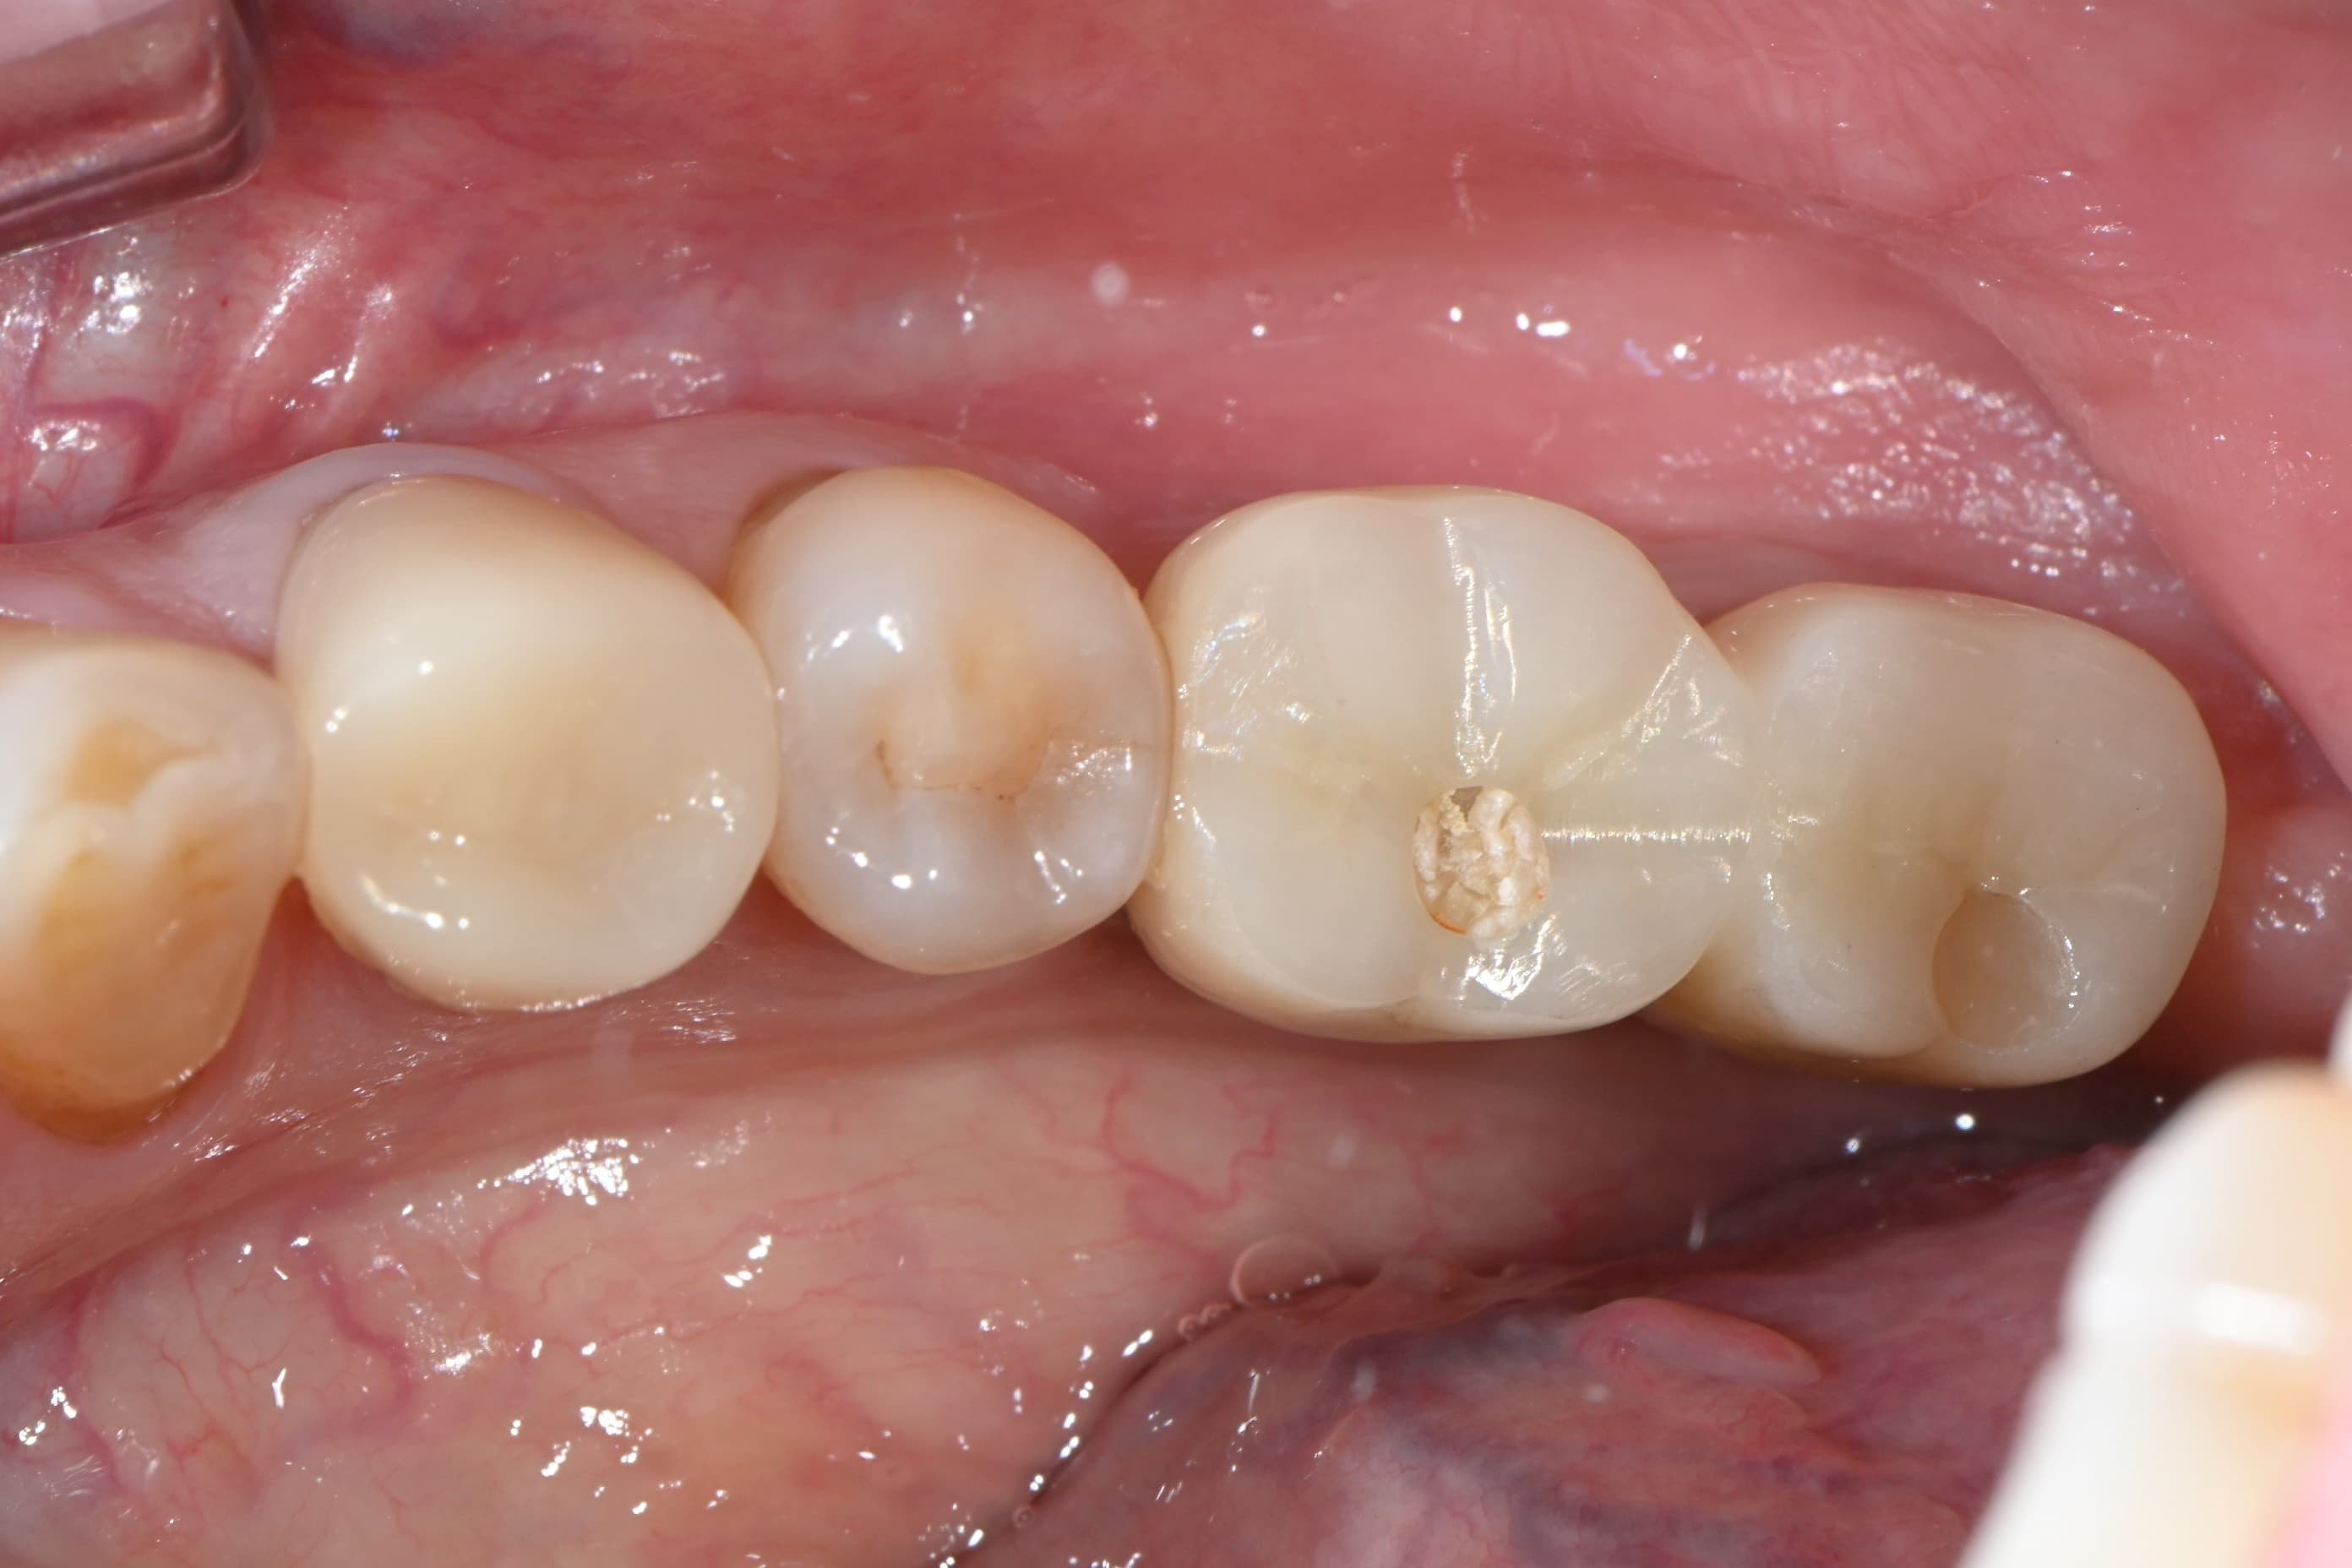

Before

임플란트 보철 · 실제사진 · 지●● · 남성

After